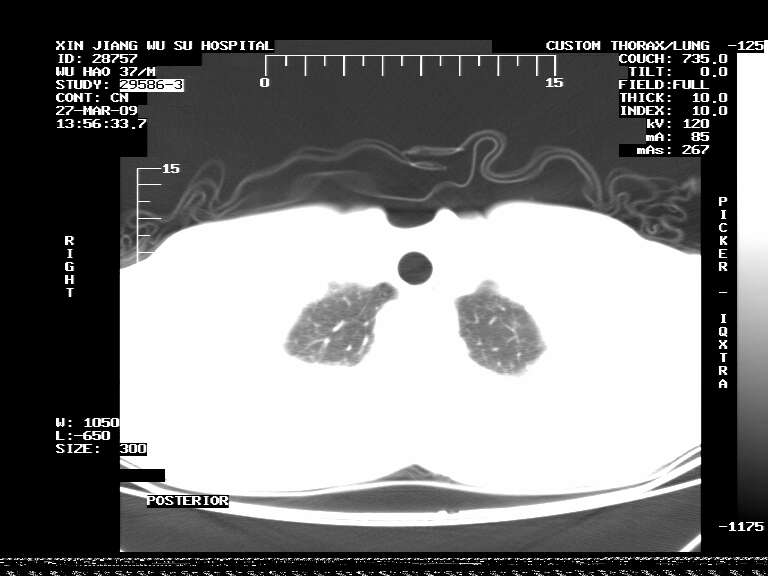

标题: CT19113:体检胸透发现阴影,CT图像。

男,37岁,体检胸透发现阴影。

患者体检发现 无症状 左肺下叶占位,边缘模糊,可见血管聚束、分叶、胸膜牵拉,增强呈不均匀性强化。 首先考虑左肺下叶周围型肺癌,建议穿刺活检。

患者体检发现 无症状 左肺下叶占位,边缘模糊,可见血管聚束、分叶、胸膜牵拉,增强呈不均匀性强化。 首先考虑左肺下叶周围型肺癌,建议穿刺活检。支持!

左肺下叶见一结节病变,边缘欠清不光滑,与胸膜粘连且胸膜局限性增厚,注药后呈环形强化,动脉期壁呈明显点环状强化,静脉期壁强化减低,中心密度低无强化,灶周无明显的卫星灶和水肿区(晕征)---考虑周围性肺癌,不除外感染性病变,建议穿刺活检。

左肺下叶软组织病灶,密度较高,内见点状钙化,其周围见子灶,邻近胸膜扁平样增厚.c+病灶强化明显,中心强化弱.诊断:左肺下叶结核瘤.